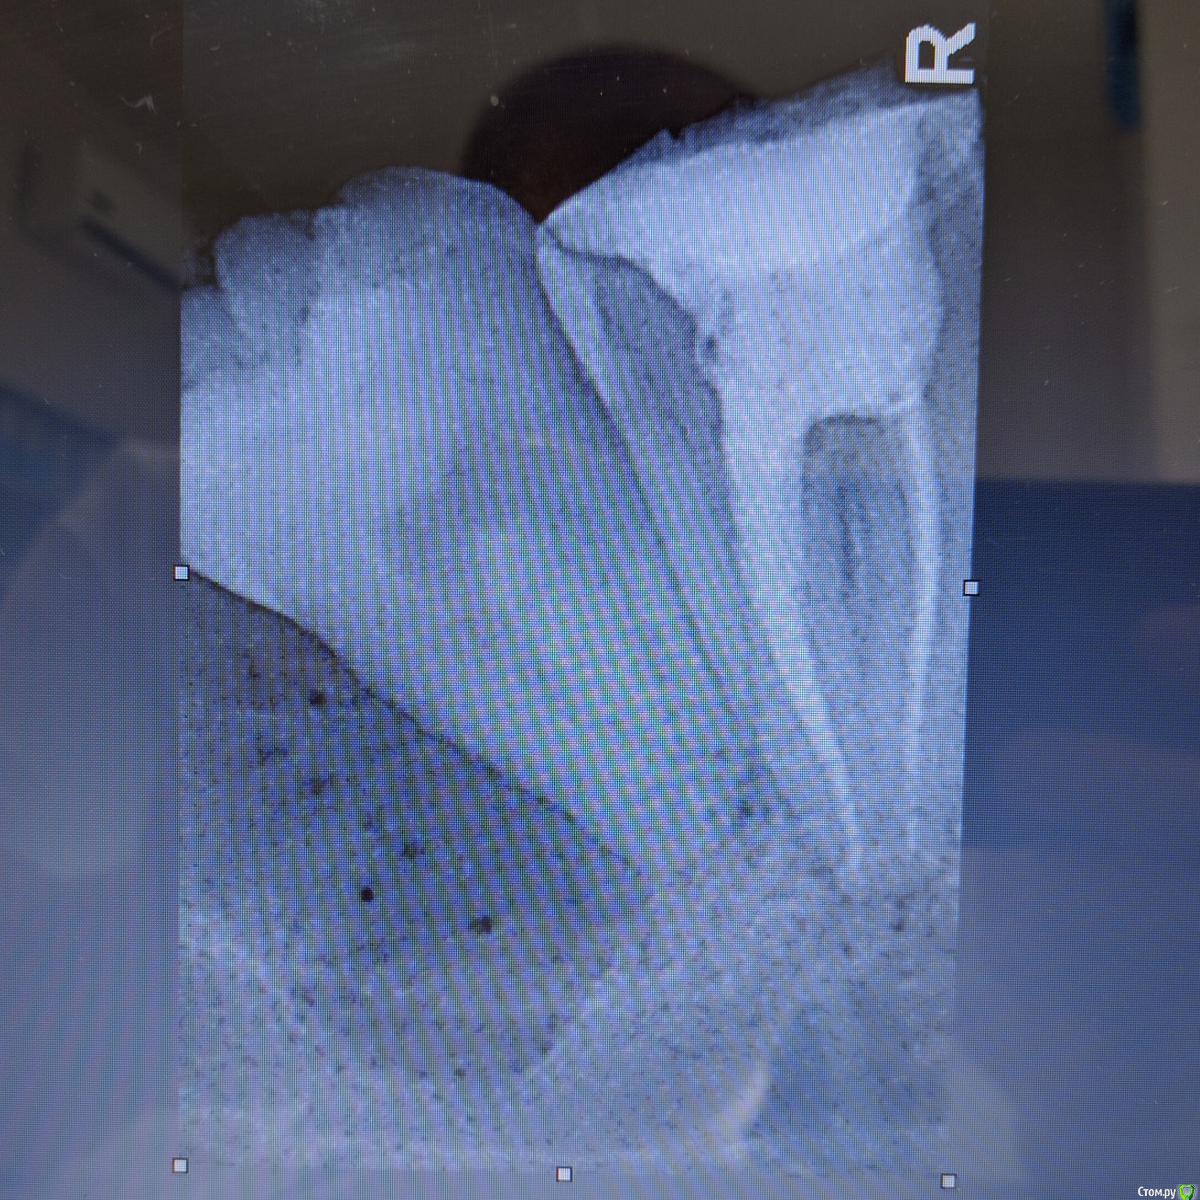

Jurai Опубликовано 29 декабря, 2016 Поделиться Опубликовано 29 декабря, 2016 А эта восьмерка спряталась лучше всех 1 Ссылка на комментарий

diesel87 Опубликовано 30 декабря, 2016 Поделиться Опубликовано 30 декабря, 2016 А эта восьмерка спряталась лучше всехIMG-20161228-WA0002.jpegIMG-20161228-WA0006.jpegIMG-20161228-WA0004.jpegСерьезно легла, убирать будете? Ссылка на комментарий

Jurai Опубликовано 30 декабря, 2016 Поделиться Опубликовано 30 декабря, 2016 А зачем, это случайная находка. Пусть лежит. 1 Ссылка на комментарий